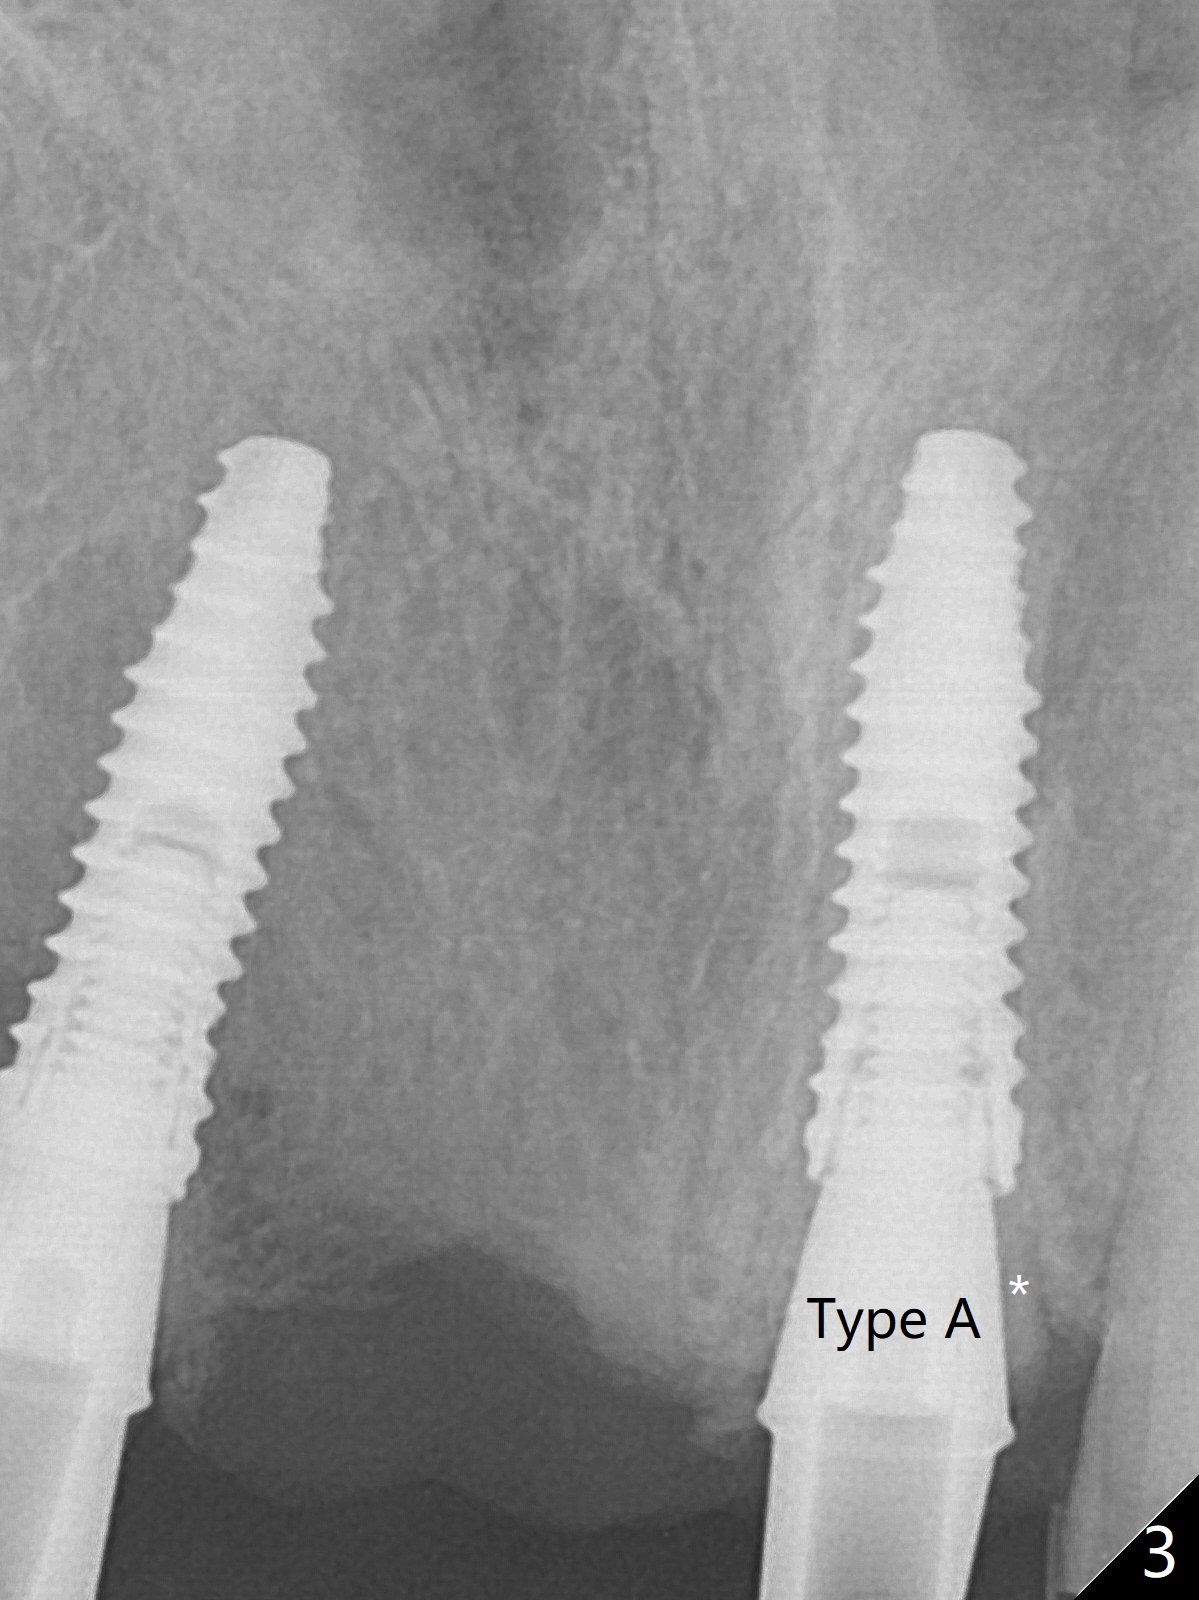

Since the pontic (Fig.1 #8) of the existing failed FPD has severe buccal concavity (*), socket shield is performed when #7 and 9 are extracted (Fig.2,3 *). Angled abutments are placed when 3.5x13 mm implants are inserted with guide. An immediate provisional FPD is fabricated. Acrylic is added to the pontic of the temporary FPD (Fig.4 arrow) to form a concave pontic gingiva (blanch)16 days postop. The patient returns 3.5 m postop with concern over temp being bulky and turning yellow. With Cetacaine and 1-0 cord, labial reducion is done for 7,9 abutments as well as 7 incisal reduction. The provisional is relined to increase 7 8 crown length. Next visit we will continue modification of temporary. Photos will be taken before and after modification (buccal and incisal views). The patient complains of occasional pain at #7. Check whether the socket shield at #7 is a culprit. In fact the implant at #7 is normal. Manipulation of the provisional does not help cosmetics much. A permanent restoration is delivered 5.5 months postop (Fig.7-9).